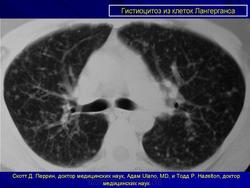

Лёгочный гистиоцитоз

http://www.ojrd.com/content/7/1/16